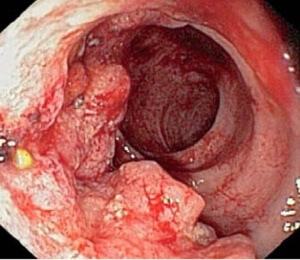

- Эндоскопия. Зонд помогает визуализировать сами пузырьки, отличить их от повышенного газообразования и уточнить диагноз.

Пневматоз кишечника. Патологический процесс, при котором в стенке кишечника образуются воздушные кисты. Заболевание проявляется спазмами, разлитой болью и чувством распирания в желудке. Отмечается расстройство стула, тошнота, отрыжка, рвота. Диагностические мероприятия включают осмотр гастроэнтеролога, обзорную рентгенограмму брюшной полости, ирригоскопию и колоноскопию. В зависимости от преобладающих симптомов пневматоза назначают ветрогонные, спазмолитические, слабительные или противодиарейные средства, диетическое питание со сниженным потреблением газообразующих продуктов.

- ирригоскопия. Определяет избыток газа в расширенных петлях толстой кишки в виде нескольких смежных округлых теней, разделенных стенкой. В процессе исследования можно обнаружить участки уменьшенного просвета, патологические новообразования, изъязвления кишечной трубки;

- колоноскопия. Эндоскопический метод позволяет визуализировать пузырьки газа, оценить степень поражения и состояние слизистой оболочки ЖКТ. При необходимости выполняется биопсия участка кишечника для гистологического анализа.